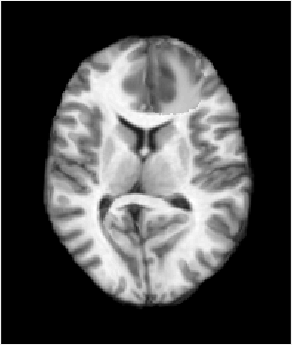

[Uncaptioned image] [Uncaptioned image] [Uncaptioned image] [Uncaptioned image]

[Uncaptioned image] [Uncaptioned image] [Uncaptioned image]

(a) (b) (c) (d)

Fig. 6: Example BRATS reconstructions: (a) tumor image; (b)-(d) reconstructions (top) and tumors (bottom); (b) PCA model w/o regularization; (c) PCA model w/ one and (d) w/ two regularization steps.

Fig. 6 shows decomposition results for our PCA models. We pick γ=5.0𝛾5.0\gamma=5.0 for the model without and γ=2.0𝛾2.0\gamma=2.0 for models with regularization. The goal is to allocate as much of the tumor as possible to the abnormal part, S𝑆S, while keeping the normal tissue in the quasi-normal part of the decomposition. Qualitatively, our models identify tumor/normal areas, while retaining image details in normal tissue areas.